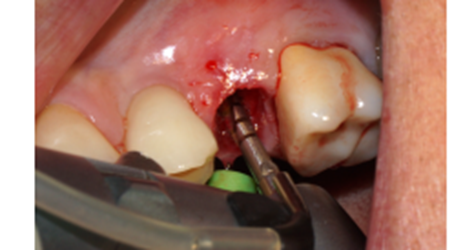

Foi eleito um implante Veloce Cone Morse de 3.75 X 11.5 mm e após a exodontia, o implante foi instalado utilizando o protocolo de fresagem recomendado pelo fabricante, fazendo uso das fresas escalonadas do sistema, alcançando um torque de inserção de 70 Ncm, o que me incentivou a promover o carregamento imediato deste implante (Figuras 5, 6, 7, 8, 9 e 10).